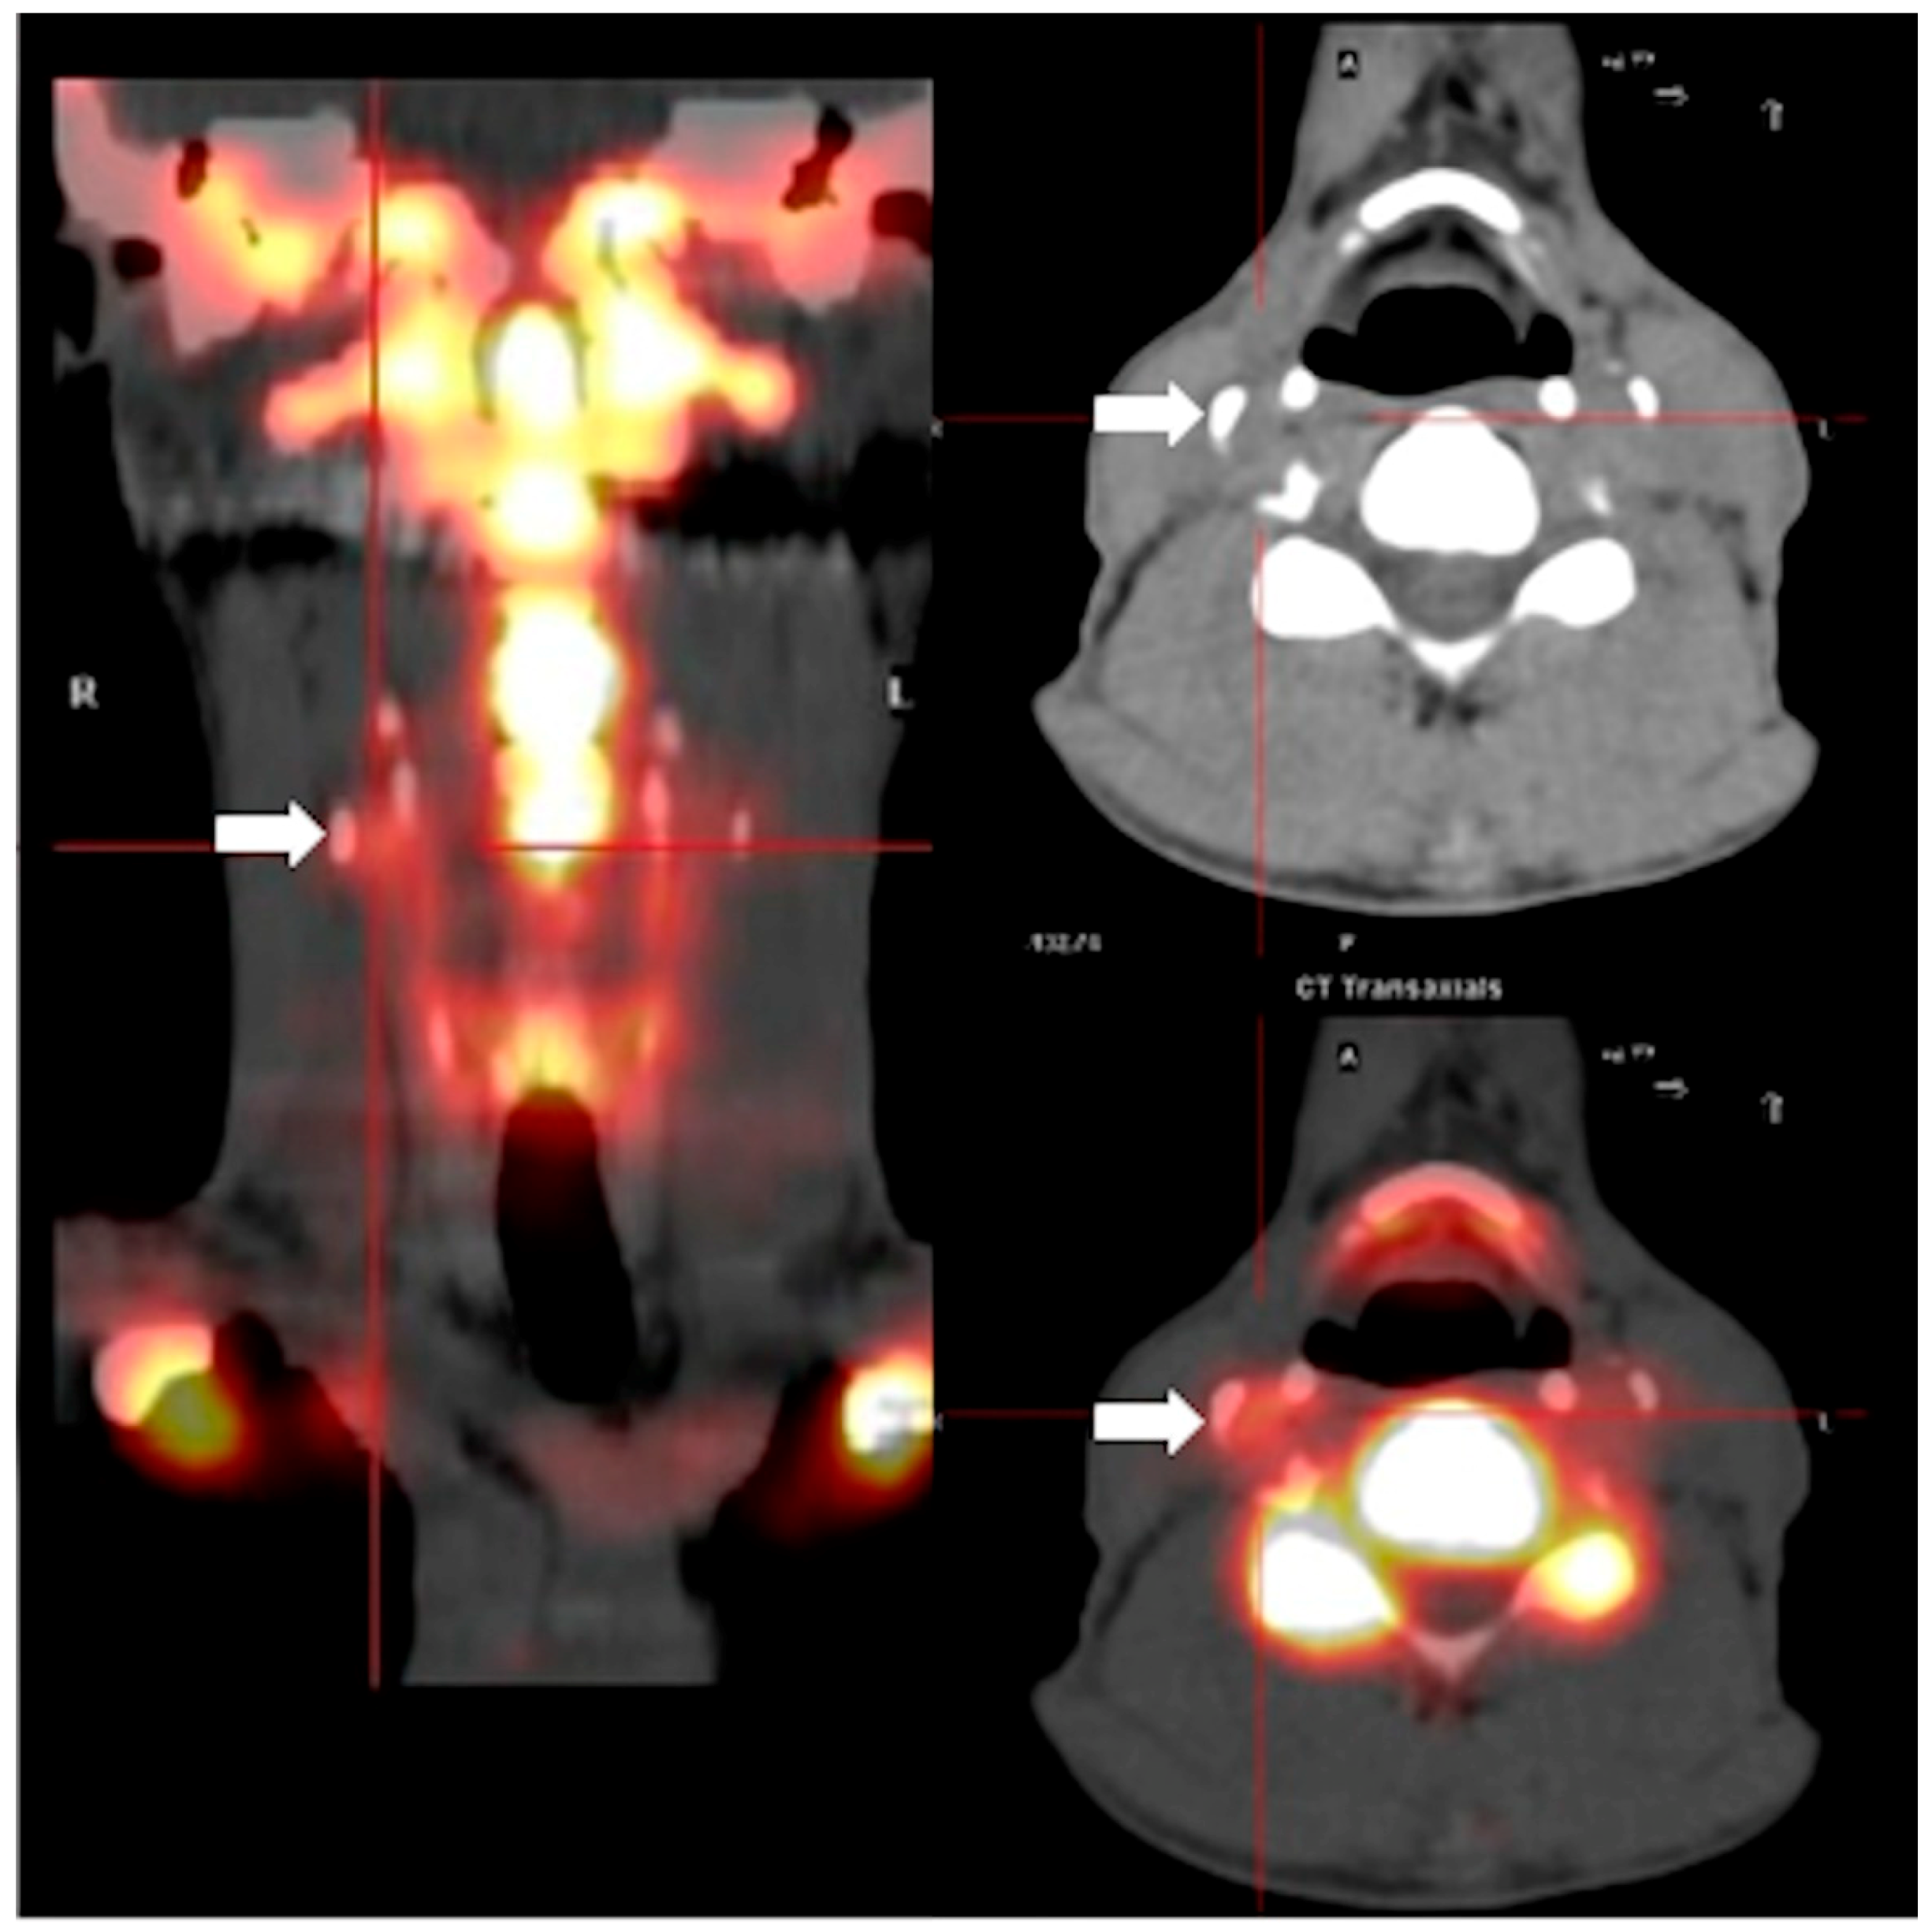

4.3.2. Positron Emission Tomography with 18F-Sodium-Fluoride